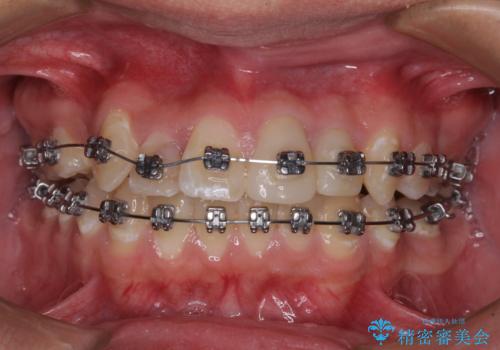

- 矯正装置

- メタルブラケット

- 治療期間

- 2年6ヶ月

矯正治療は、むし歯が酷く抜歯が望ましい歯を1本抜歯して、ワイヤー装置にて整えることとしました。

むし歯が多かったため、ワイヤー矯正中に処置したむし歯が悪化することが懸念されましたが、歯磨きをしっかりと行ってくれたため、とても良好な状態を維持することができました。